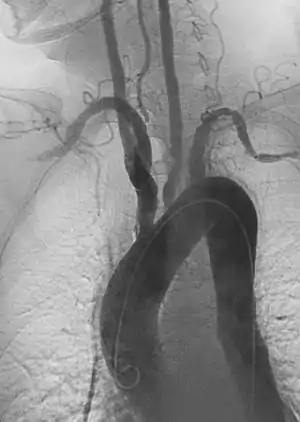

بررسیهای اولتراسوند با استفاده از داپلر برای نشان دادن درگیری عروق نزدیک به قلب مفید است ولی غالباً قادر به نشان دادن درگیری رگهای محیطی تر نمیباشد. غالباً مشاهده کلیه رگهای اصلی توسط (pan-aortography) و در مورد رگهای ریه (pulmonary angiography) لازم است تا بتوان وسعت درگیری عروقی را ارزیابی نمود.